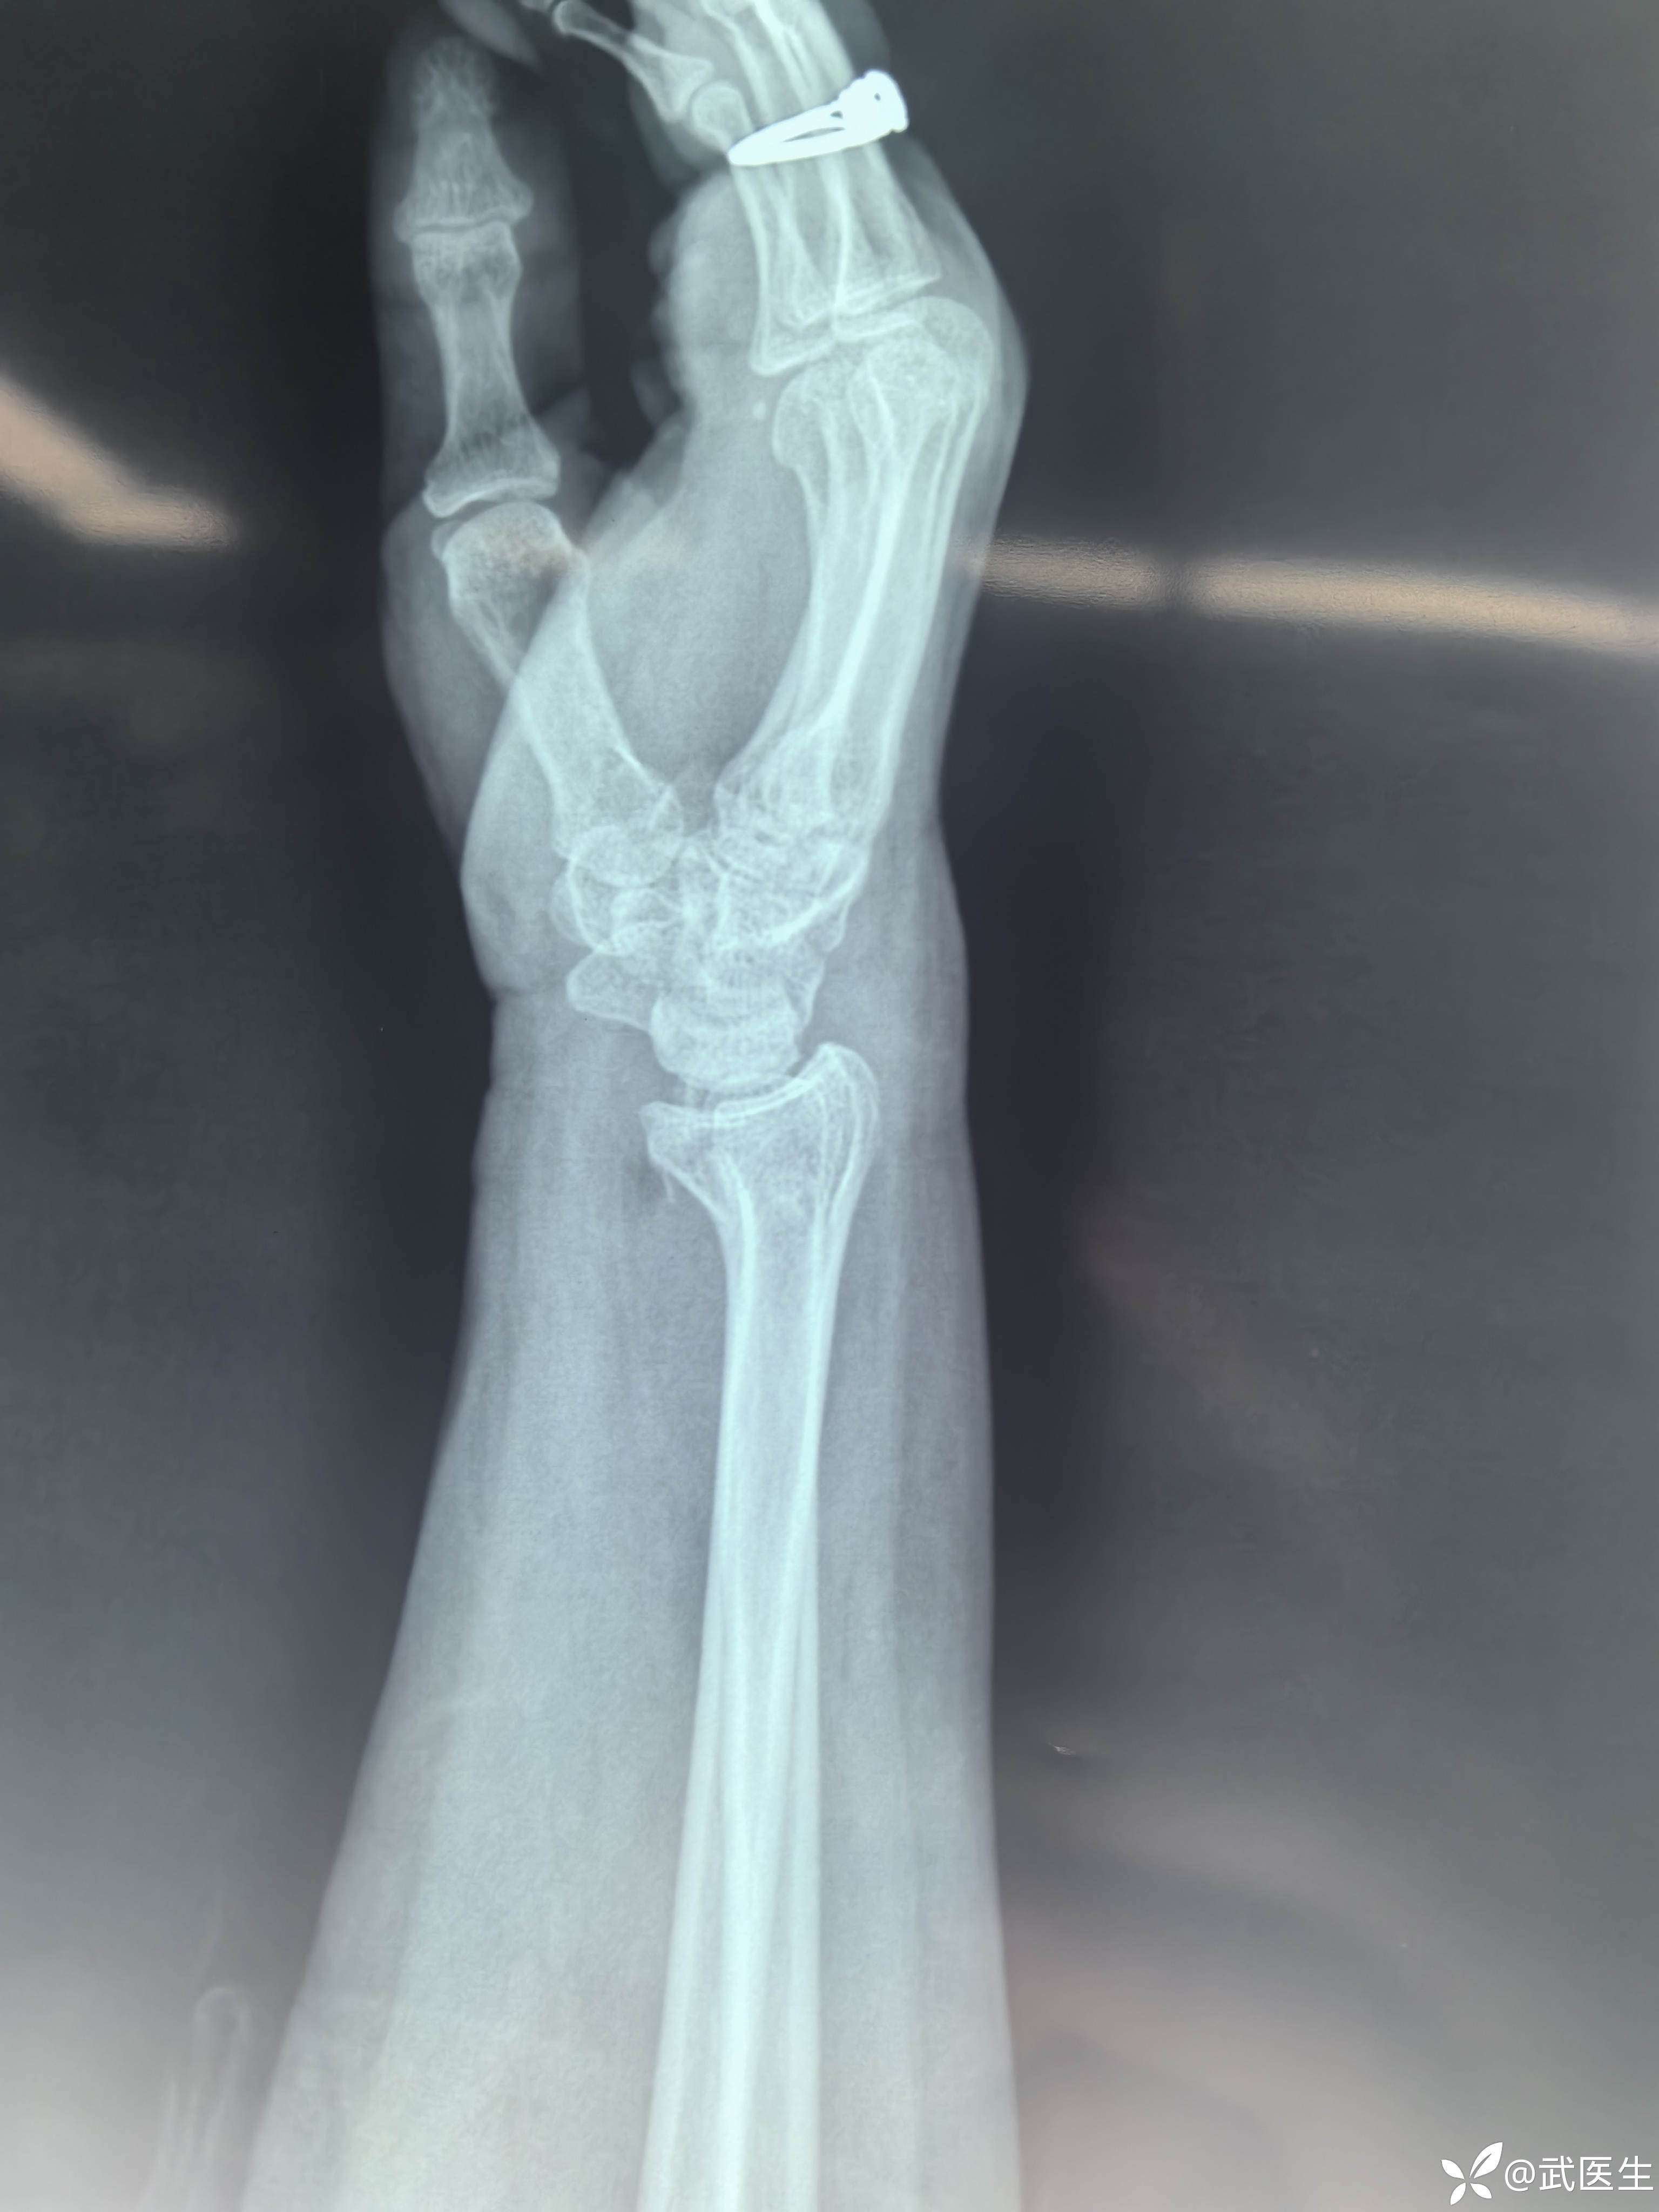

【主诉】:摔伤致右肩,左腕疼痛畸形,头面部皮肤挫伤一小时

腕关节片子系外院带来

【临床诊断】:右肱骨外科颈四部分骨折脱位,左桡骨远端骨折伴桡腕关节半脱位。钩骨骨折。头面部软组织损伤。